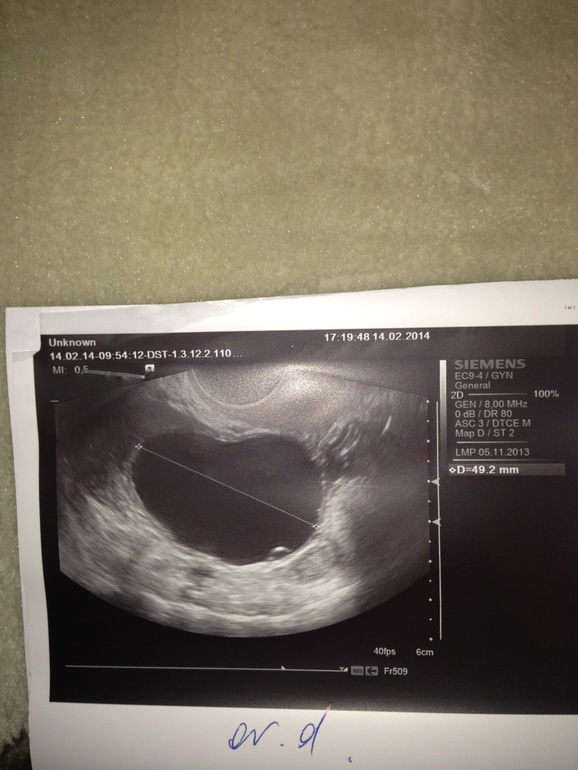

На 15 дц был 49мм, большой какой-то(((

Кошмар....какой же это фолликул??? Это киста....причем за которой нужно наблюдать, чтобы она не разорвалась...это опасно для жизни вообще, чревато кровотечением.Вы ничего не путаете? Можете сфотографировать заключение УЗИ?

слушай (ничего, что на ты?), меня аж разрывает от этих узистов!!! Какой ДФ 49 мм...может она ошиблась? Опечатка..... 19 наверное....посмотри на снимок этого яичника и справа там цифры есть...размеры...или тоже сфоткай

Наташ, это киста!!! Иди к гинекологу своему....и читай выше что я писала про кисту(((( Пипец, переживаю...Короче у меня была такая, 3 месяца без М, потом начало мазать черным.....я к Г, а он прописал кровоостанавливающее.....короче мне повезло и она рассосалась....тебе нужно наблюдать!!!

Да ладно? А я когда увидела узи подумала что это размер яичника(((и узистка ошиблась.

Ну во первых с чего такой большой яичник? во вторых где в нем фолликулы? И в третьих в заключении написано ДФ 49 мм.....я до сих пор в шоке от неё.....